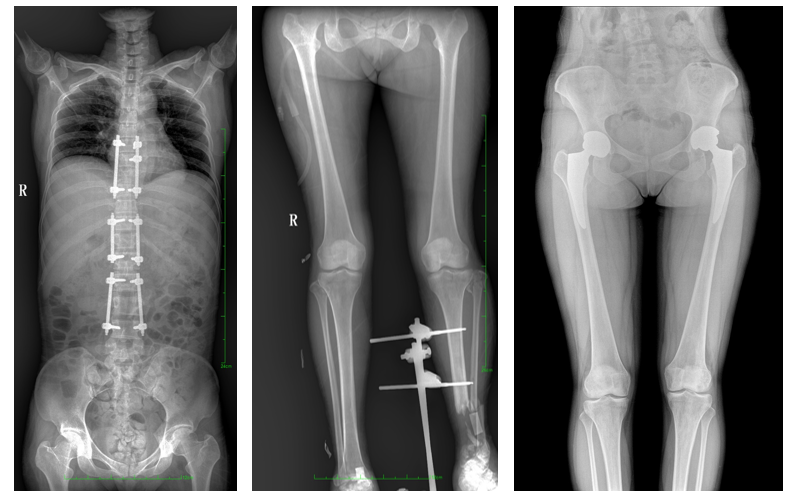

DR常用于人體胸部及骨骼攝片,也可拍攝其他部位,例如腹部、牙齒、頭顱等。使用人群較廣,可以進行全身各部位檢查,曝光后幾秒就可獲得數(shù)字影像,成像速度快,且價格便宜,極大提高了工作效率,方便臨床重癥、急癥患者的診治。

站立位X線影像是測定人體負重骨骼的生物學力線、對稱結構平滑線及脊柱側凸角等首選的檢查內容,這和CT、MRI臥位成像,在臨床意義上有著根本區(qū)別。在脊柱及下肢的臨床治療過程中,一般需要進行矯正和關節(jié)置換手術治療,在對其進行手術前后,均需要拍攝站立位負重X光片以便分析病情,明確診斷和觀察治療效果。

常規(guī)DR拍攝面積有限,最大規(guī)格僅有43cm,但成人男性全脊柱長度平均為70-75cm,女性為66-70cm,而雙下肢更長。普愛醫(yī)療PLX8600動態(tài)DR的43cm*86cm超大有效視野,可一次成像全脊柱及雙下肢。